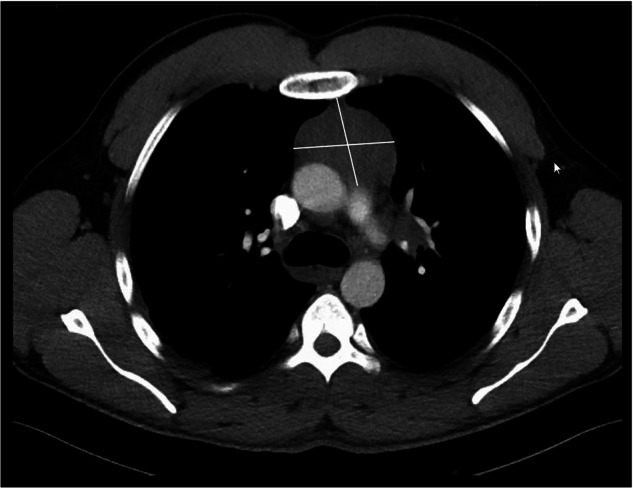

急性髓性白血病(AML)伴PICALM::MLLT10重排是一种罕见且特征不明确的疾病。在这里,我们描述一个病人与这种重排,并比较这个情况下的文献。我们观察到年轻、男性、髓外受累(特别是纵隔髓肉瘤)、4三体、19三体和cd7异常表达的趋势。这表明dot11或BMI1的上调是随后白血病发生的关键效应因子。然而,大多数已发表病例的分子数据不可用。有趣的是,在我们的病例中检测到两种不同的ezh2突变,而在AML中通常是罕见的,这与最近关于EZH2mut在该AML亚型中发生的报道一致。由于BMI1和EZH2的协同作用已经在其他肿瘤中得到证实,我们假设获得EZH2突变可能是PICALM::MLLT10阳性细胞增殖的关键优势。这可能解释了该实体中EZH2突变病例的高比例,但也支持了bmi1介导的白血病发生的假设。

Acute Myeloid Leukemia (AML) with rearranged PICALM::MLLT10 is a rare and poorly characterized entity. Here, we describe a patient with this rearrangement, and compare this case to the literature. We observed a trend towards young age, male sex, extramedullary involvement (particularly mediastinal myelosarcoma), trisomy 4, trisomy 19 and aberrant CD7-expression. It was suggested that upregulation of DOT1l or BMI1 is a key effector for subsequent leukemogenesis. However, molecular data are not available for most published cases. Interestingly, two different EZH2-mutations were detected in our case, while generally being rare in AML, which is concordant with recent reports on the occurrence of EZH2mut in this AML subtype. As a synergistic effect of BMI1 and EZH2 has already been demonstrated in other neoplasms, we hypothesize that acquiring an EZH2 mutation might be a crucial proliferation advantage in PICALM::MLLT10 positive cells. This may explain the high percentage of EZH2 mutated cases in this entity, but also supports the hypothesis of BMI1-mediated leukemogenesis.